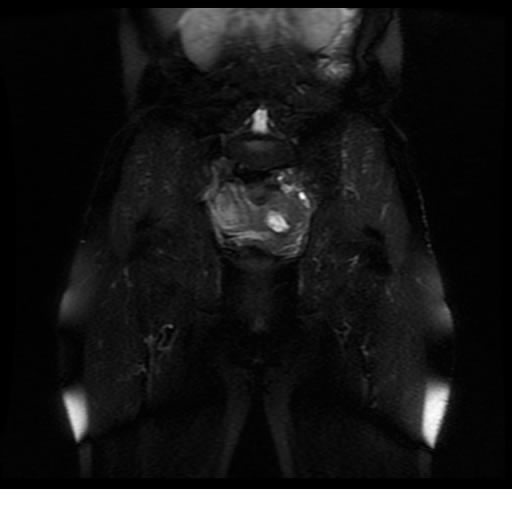

Se realizan adquisiciones en diferentes planos, con secuencias Spin echo y GRE, ponderadas a T1 y a T2, se utilizan pulsos de saturación de grasa y se administra medio de contraste a base de gadolinio.

El útero está en retroversión, retroflexión, y en posición central, se observa liquido en la cavidad endometrial, debido a la presencia de un Ca endometrial; en el anexo derecho se observa una masa quística que mide 3.8 x 2.2 cm de diámetro, corresponde a un quiste bilobulado, posee pared gruesa con componente solido puede tratarse de un Cistoadenocarcinoma, el cual realza con el medio de contraste de forma importante, entra dentro de una clasificación O-Rad tipo IV compatible con un Cistoadenocarcinoma

O-RAD tipo IV, Cistoadenocarcinoma